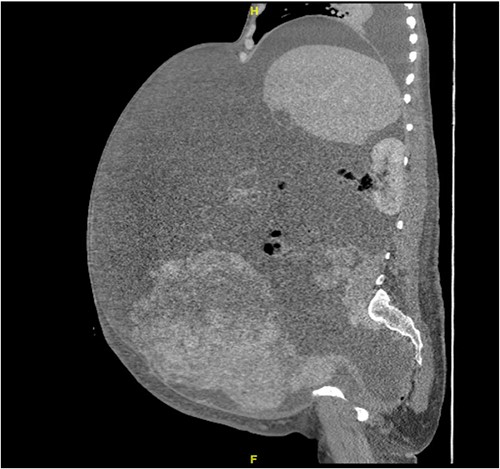

A 40-year-old Saudi, nulliparous woman, medically free with a history of leiomyoma (uterine fibroid) underwent myomectomy. She was referred to our center as a case of large abdominopelvic mass, tense ascites and pleural effusion. The patient complained of the shortness of breath, palpitation, marked abdominal discomfort and bloating as well as back pain. She reported that she first noticed the bloating 3 months prior to the visit. However, she was unable to come because of COVID-19 pandemic situation. She is a housewife; never smoked tobacco or drank alcohol, and had no history of recent travel to endemic or pandemic areas. On further investigations, a serum CA-125 was found to be elevated 492.6 U/mL (normal < 35 U/mL), whereas the concentration of other tumor markers LDH, CEA, CA19-9 and ALP was within normal ranges. Abdominal CT scan revealed a significant interval increase in the size of ascites, which caused a huge abdominal distention along with severe mass effects on the abdominopelvic organs, which have been displaced posteriorly as shown in Fig. 1. In addition, it revealed a large exophytic uterine fibroid measuring 15 × 20 × 17.5 cm. A therapeutic paracentesis was done with the removal of 50.750 ml of ascitic fluid. Figure 2 shows how pleural effusion is markedly significant. A total abdominal hysterectomy, with bilateral salpingo-oophorectomy and omentectomy, was performed. Intraoperative finding revealed a very large mass, which originated from uterine fundus. The pleural effusion and ascites disappeared entirely after the excision of abdominopelvic mass. She recovered completely and went through an uneventful postoperative period. On pathology of surgical specimens, a giant uterine leiomyoma with degenerative changes, pleural and ascitic fluids was yielded negative for malignancy and diagnosed as a benign mesothelial proliferation, whereas H&E stain of the omentum excision surprisingly confirmed multiple, large and irregular disorganized veins (thin-walled blood vessels) and arteries (thick-walled blood vessels), some with organized thrombi consistent with omental AVM as shown in Figs 3 and 4. Provisional diagnosis of pseudo-Meigs’ syndrome with omental AVM was considered.